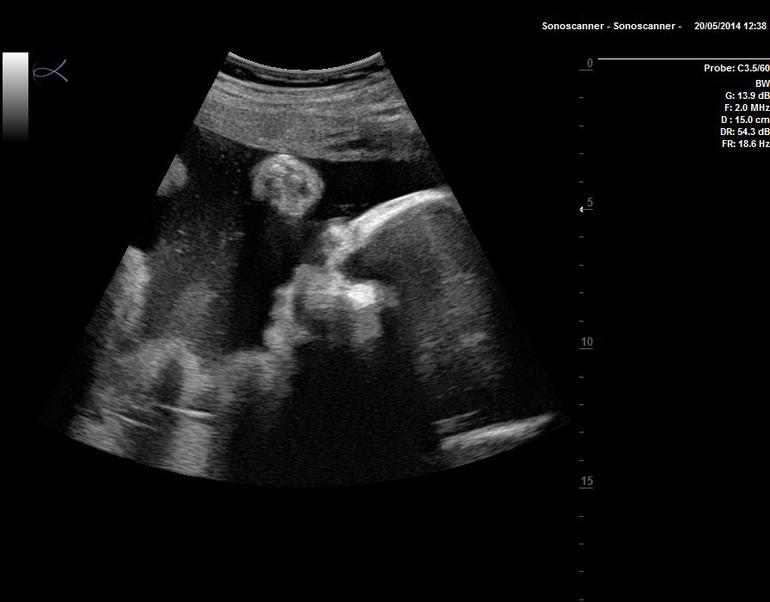

Третье УЗИ

О хорошемИ так сегодня 32 недели и 4 дня..Божечки как быстро летит время..сегодня с мужем ходили на третье УЗИ..увидели нашего сыночка..Мардастенький,носик папкин..40 сантиметров, вес 2100.Все у нас хорошо обвития пуповиной нет, лежит головкой вниз.. В общем уже с нетерпением ждем встречи..